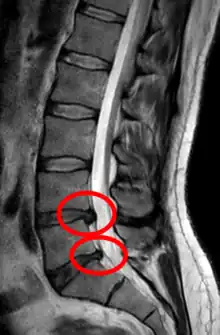

• Magnetic resonance imaging is the gold standard study for confirming a suspected LDH. With a diagnostic accuracy of 97%, it is the most sensitive study to visualize a herniated disc due to its significant ability in soft tissue visualization. MRI also has higher inter-observer reliability than other imaging modalities. It suggests disc herniation when it shows an increased T2-weighted signal at the posterior 10% of the disc. Degenerative disc diseases have shown a correlation with Modic type 1 changes. When evaluating for postoperative lumbar radiculopathies, the recommendation is that the MRI is performed with contrast unless otherwise contraindicated. MRI is more effective than CT in distinguishing inflammatory, malignant, or inflammatory etiologies of LDH. It is indicated relatively early in the course of evaluation (<8 weeks) when the patient presents with relative indications like significant pain, neurological motor deficits, and cauda equina syndrome. Diffusion tensor imaging is a type of MRI sequence used for detecting microstructural changes in the nerve root. It may be beneficial in understanding the changes that occur after herniated lumbar disc compresses a nerve root, and might help in differentiating the patients that need surgical intervention. In patients with a high suspicion of radiculopathy due to lumbar disc herniation, yet the MRI is equivocal or negative, nerve conduction studies are indicated.[44] T2-weighted images allow for clear visualization of protruded disc material in the spinal canal.

The majority of spinal disc herniations occur in the lumbar spine (95% at L4–L5 or L5–S1).[21] The second most common site is the cervical region (C5–C6, C6–C7). The thoracic region accounts for only 1–2% of cases. Herniations usually occur postero-laterally, at the points where the annulus fibrosus is relatively thin and is not reinforced by the posterior or anterior longitudinal ligament.[21] In the cervical spine, a symptomatic postero-lateral herniation between two vertebrae will impinge on the nerve which exits the spinal canal between those two vertebrae on that side.[21] So, for example, a right postero-lateral herniation of the disc between vertebrae C5 and C6 will impinge on the right C6 spinal nerve. The rest of the spinal cord, however, is oriented differently, so a symptomatic postero-lateral herniation between two vertebrae will impinge on the nerve exiting at the next intervertebral level down.[21]

Lumbar disc herniations occur in the back, most often between the fourth and fifth lumbar vertebral bodies or between the fifth and the sacrum. Here, symptoms can be felt in the lower back, buttocks, thigh, anal/genital region (via the perineal nerve), and may radiate into the foot and/or toe. The sciatic nerve is the most commonly affected nerve, causing symptoms of sciatica. The femoral nerve can also be affected and cause the patient to experience a numb, tingling feeling throughout one or both legs and even feet or a burning feeling in the hips and legs.[22] A herniation in the lumbar region often compresses the nerve root exiting at the level below the disc. Thus, a herniation of the L4–5 disc compresses the L5 nerve root, only if the herniation is posterolateral.